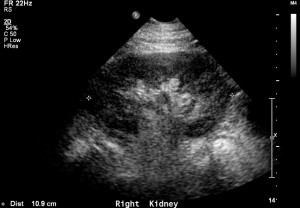

The first images to take from the flank are of the kidney in the longest view possible. In this view the kidney length and cortex should be evaluated. Sometimes part of the kidney is obscured by the rib cage. In these cases asking the patient to take a deep breath and hold will allow for better visualization.

Adding color flow to this view will give a rough estimate of blood flow to the kidney. Before doing so make sure your color scale is set to low flow.

Then, measurements should be taken from the various parts of intra-renal flow. Typically blood flow velocity is sampled in the cortex, medulla and hilum. Cortical and medullary flow should be sampled in the upper and lower poles. A zero angle can be used. These measurements serve to calculate the resistive index.